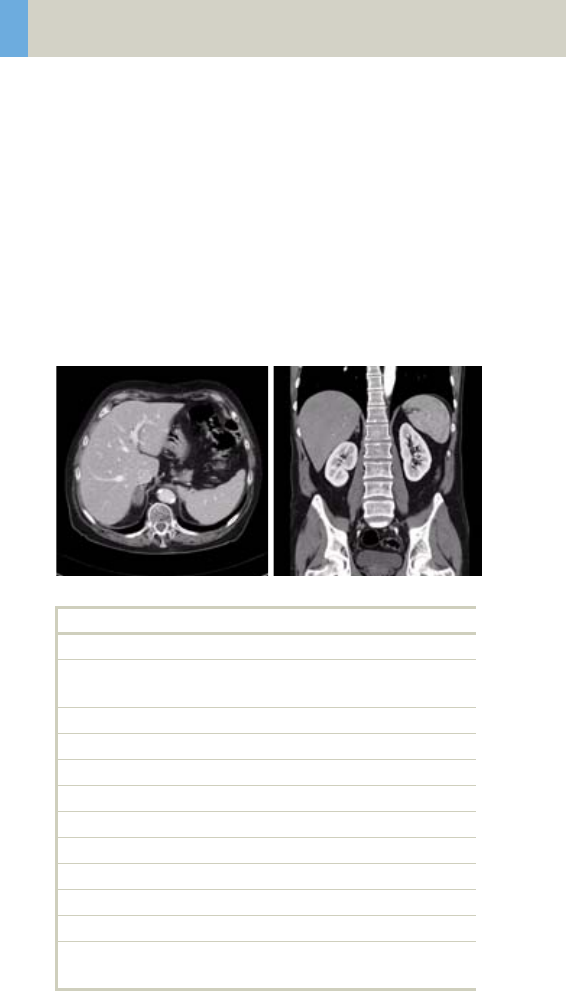

Abdomen 262

•Overview 262

- General Hints 264

- Body Kernels 265

•Scan Protocols 266

- AbdomenRoutine/

AbdomenRoutine06s 266